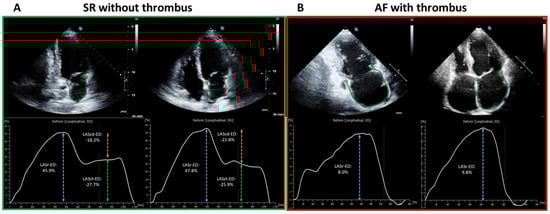

4.2. Left Atrial Appendage Thrombus Is Associated with Impaired Mechanical Function

5.2. General and Rhythm-Specific LA-GLS Thresholds for Left-Atrial Appendage Thrombus